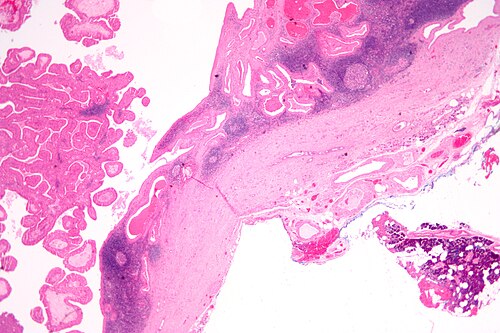

59 year old man, mass lesion

Site

Left parotid

Intermediate magnification

Intermediate magnification. H&E stain.